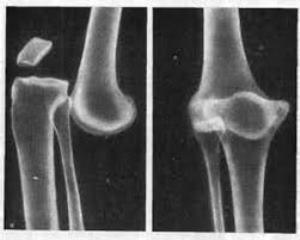

Для уточнения диагноза вывиха костей голени, кроме осмотра врача-травматолога, могут потребоваться дополнительные исследования:

- рентгенография коленного сустава и голени;

- МРТ или КТ колена;

Диагностика вывиха голени обычно включает физический осмотр, где врач оценивает состояние сустава и степень боли. Для подтверждения диагноза могут быть назначены рентгенографические исследования, которые помогут исключить переломы и определить степень вывиха.